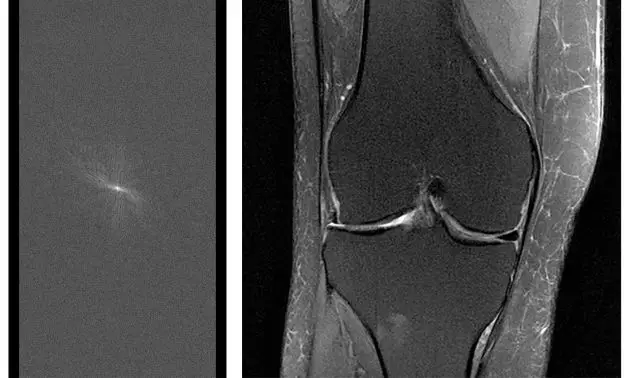

(L)在转换为图像之前的原始 MRI 数据。为了获得诊断研究所需的完整原始数据,MRI 扫描通常需要 15-60 分钟。(R)从完全采集的原始数据重建的膝关节 MRI 图像。